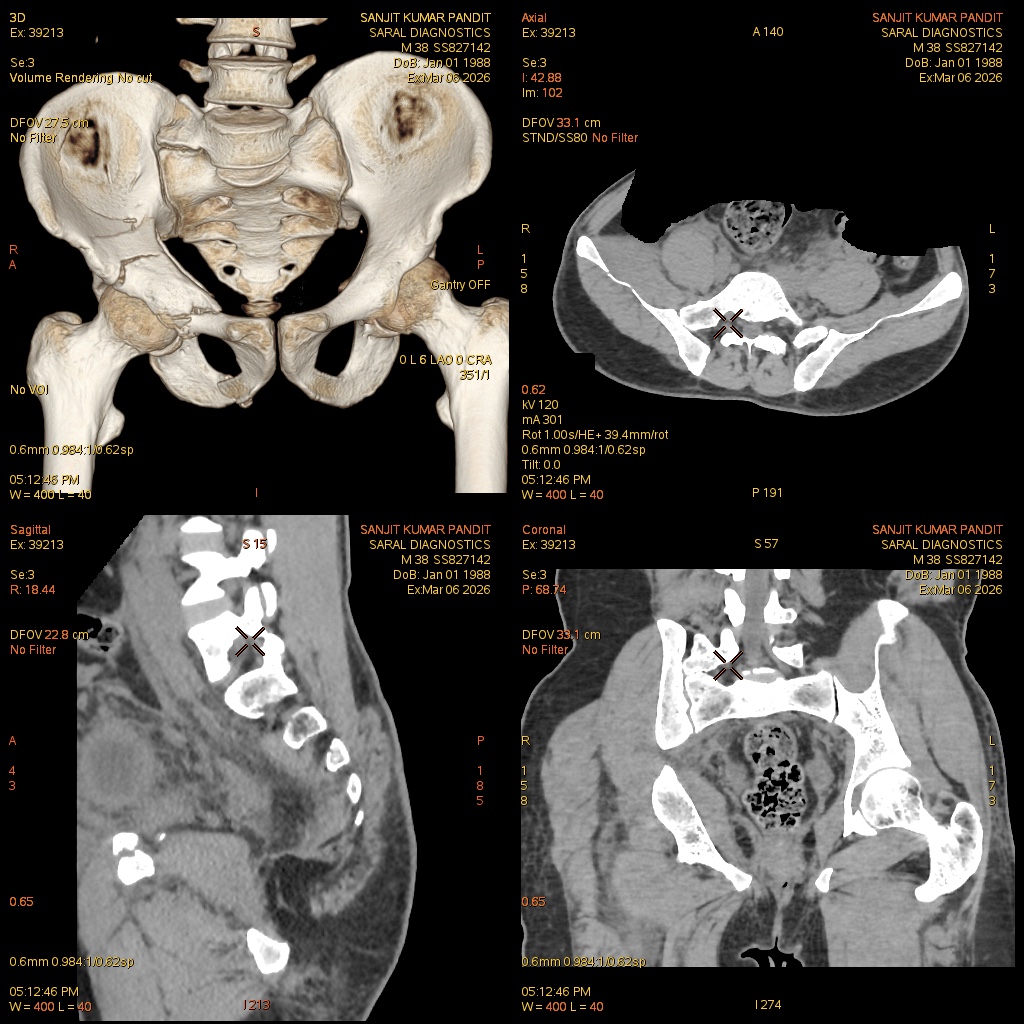

Reference Image

Pelvis (Bony) With Both Hip Joint (Scan Charges Only)

The Pelvis (Bony) With Both Hip Joint (Scan Charges Only) study is a non-contrast imaging procedure focused on evaluating the pelvic bones and both hip joints in detail. This scan provides high-resolution images of the pelvic ring, sacroiliac joints, acetabulum, femoral heads, and surrounding bony structures. Without the use of contrast material, the study is ideal for assessing fractures, dislocations, degenerative joint disease, congenital abnormalities, arthritis, avascular necrosis, and post-traumatic changes. It is commonly recommended for patients experiencing persistent hip pain, limited mobility, difficulty walking, or after injuries such as falls or accidents. The scan also helps detect subtle bony lesions and early degenerative changes that may not be visible on regular X-rays. Orthopedic specialists use this study for pre-operative planning, follow-up after surgery, and evaluation of chronic musculoskeletal conditions. Being a non-invasive and safe test, it offers a reliable method for comprehensive structural assessment of the pelvis and both hip joints.